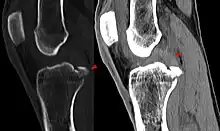

Les radios n'apportent aucune contribution immédiate au diagnostic de rupture de LC. Les deux LC sont invisibles à la radio, déchirés ou non. La seule utilité de la radio ne peut servir qu'au diagnostic des complications osseuses possibles.